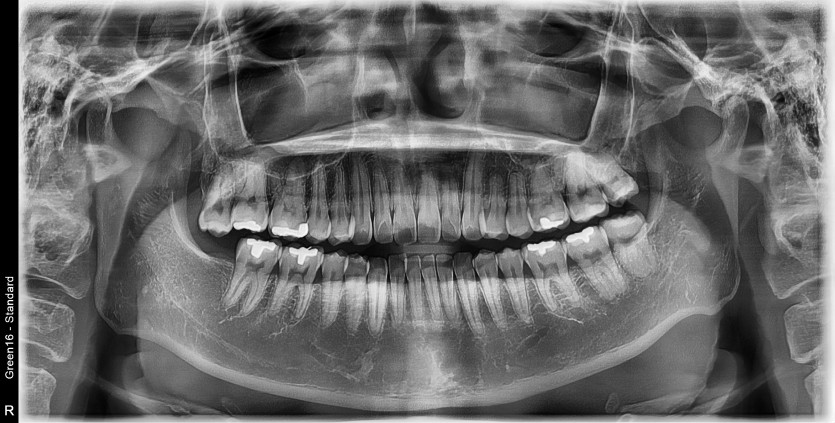

#28 사랑니 발치

구강 외과 전문의가 당일 발치했습니다.